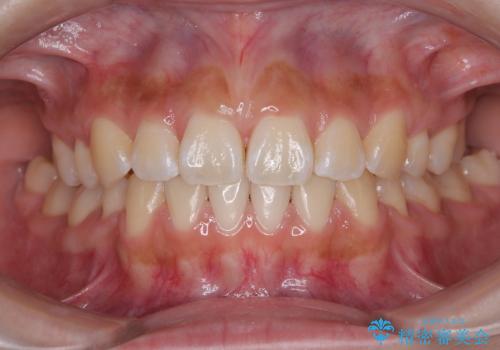

【ワイヤー矯正】八重歯 歯のでこぼこを治したい!